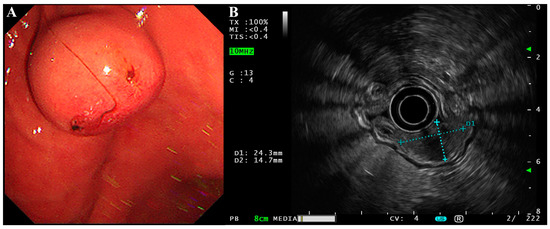

The patient was a 58-year-old male who happened to find a submucosal mass during an esophagogastroduodenoscopy (EGD) in an annual routine examination. He had no discomfort or history other than hypertension and cholecystlithiasis, and came to our hospital for further consultation and examination. We found the mass at the lesser curvature of the gastric body (2.43 × 1.47 cm, Figure 1A) with an ulceration in the center of the mucosal surface. Endoscopic ultrasonography (EUS) was then performed using a circular array (EU-ME2 PREMIER PLUS with UE260-AL5, Olympus Optical Co., Ltd., Tokyo, Japan). The mass was hypoechoic and originated from the muscularis propria with a clear boundary and uniform internal echo (Figure 1B). There was no sign of infiltrative growth as the serosa layer of the lesion was intact. It was initially thought to be a gastrointestinal stromal tumor (GIST).

Figure 1. EGD and EUS of the gastroblastoma. (A) EGD showed a submucosal mass with a small ulcer on its surface at the lesser curvature of the gastric body. (B) EUS showed the lesion was hypoechoic with a clear boundary and uniform internal echo. The lesion was approximately 2.43 × 1.47 cm in size and originated from the muscularis propria with an intact serosa layer.